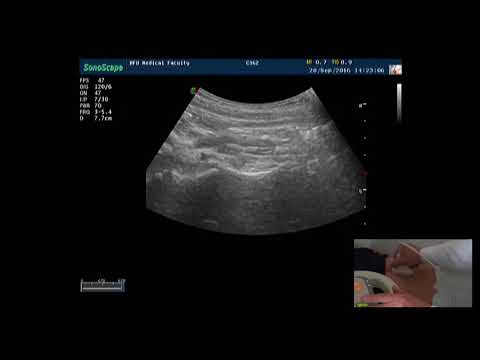

Допплерография сосудов печени. Часть 1.

Лекция для врачей ультразвуковой диагностики. Запись 25. 09. 2018 г.